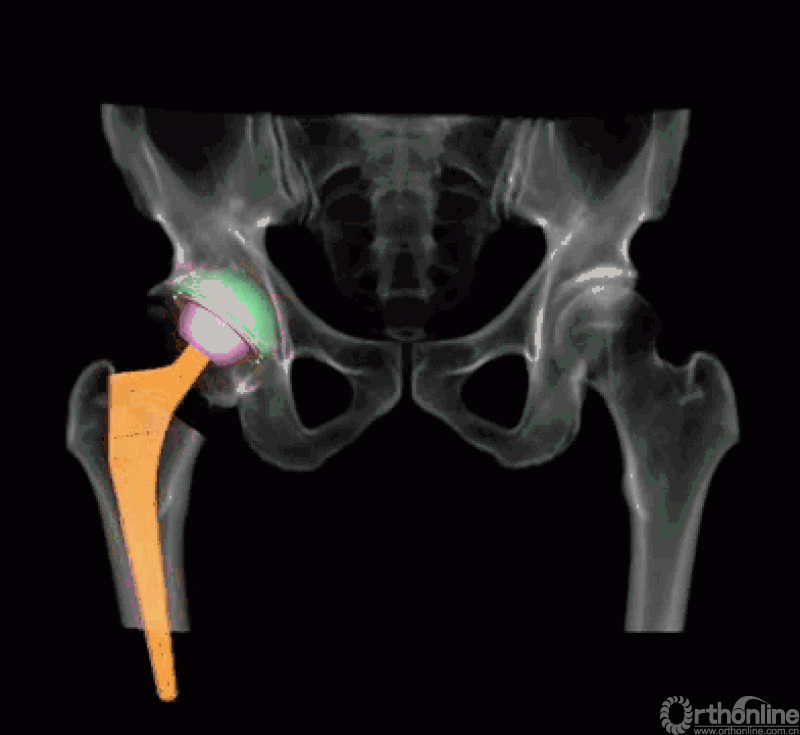

AI HIP系统智能安放54mm直径的强生Pinnalce髋臼杯

最后,AI HIP系统根据患侧股骨颈干角、偏心距偏大的特殊情况,智能选择使用高偏高颈干角假体,对下肢等长和等偏心距重建做出了精准设计。根据系统预测结果,术中使用54mm Pinnalce髋臼杯、12号CORAIL高偏股骨柄、36mm 陶瓷股骨头、小转子上23mm截骨,实现髋关节的个体化、精准化重建。

为了最大程度地保留对髋关节软组织结构的完整性和张力状态,张瑗教授采用个人擅长的直接前入路(DAA)进行手术,此入路最大程度降低髋关节术后脱位风险,另外保障了人工关节假体的精准位置。手术切皮至安装假体耗时42分钟,术中出血约100ml,术中应用假体大小与AI HIP系统术前规划完全一致,高偏心距假体保证了关节周围软组织的张力。术后复位良好,假体稳定性佳。由于切口仅为9cm,疼痛刺激轻微,加之无任何管道的妨碍,如尿管、引流管、输液管等,和患者在康复医生指导下当日下地进行活动,主观感受极佳。这些也进一步映证了新桥医院骨科关节中心MDT团队常态化推进ERAS方案的确切效果!